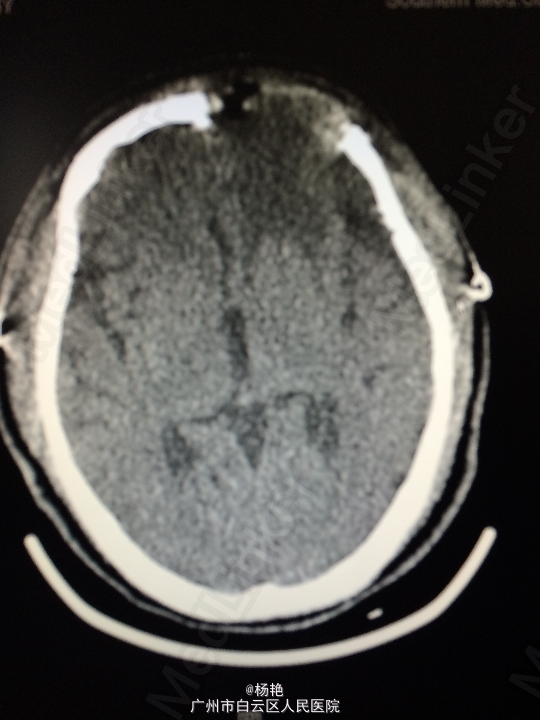

主诉:反复头痛2年加重1周 病史:患者诉两年前无明显诱因反复出现头晕头痛不适,近一周来症状加重,无恶心呕吐、无行走不稳、肢体乏力、意识障碍等。遂至当地医院诊治,行头颅CT、MR检查均提示颅内占位,良性可能性大,考虑脑膜瘤。今患者为求进一步治疗而入我院。

查体:神经系统查体未见明显异常 辅助检查:头颅MR提示:左侧额叶区域较大类圆形肿物,多考虑脑膜瘤可能;大脑前动脉及中动脉受压,中线偏移。